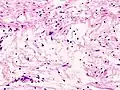

| Micrograph of a schwannoma showing both a cellular Antoni A area (top) and a loose paucicellular Antoni B area (bottom). HE stain. | |

Verocay bodies are seen histologically in schwannomas.